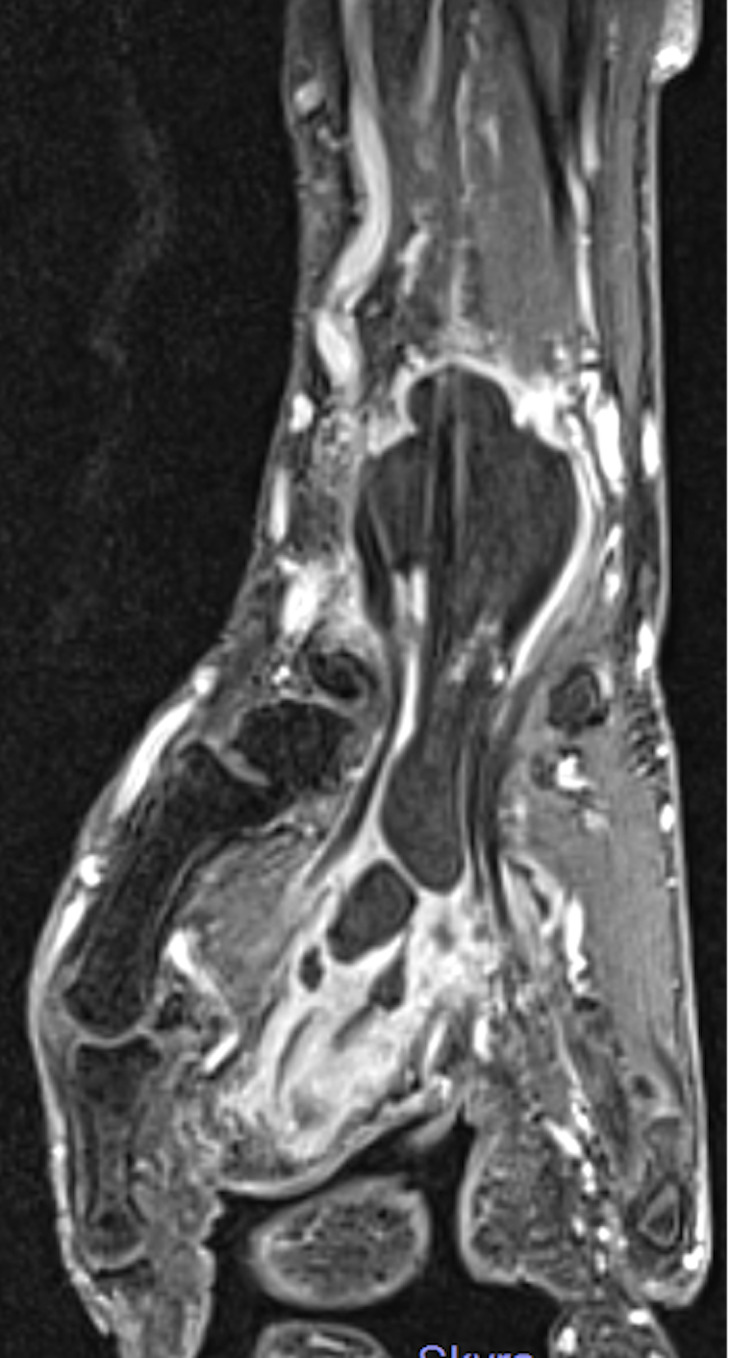

Granulomatous flexor tenosynovitis due to Mycobacterium intracellulare.

由胞内分枝杆菌引起的肉芽肿性屈肌腱滑膜炎。